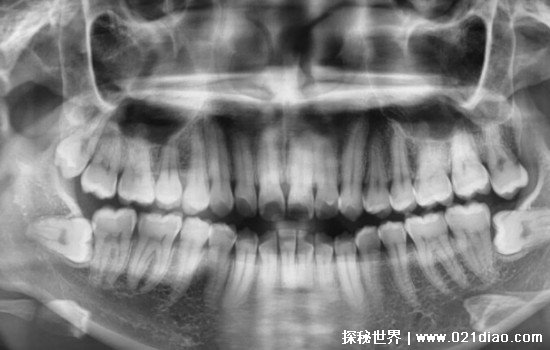

智齿是很多人都会存在的一种牙齿问题现象,对于智齿最好的解决方法就是拔掉,但是网上一直都有拔智齿后遗症太多了后悔了等说法。的确是有一些人出现了问题,例如干槽症,这让一些人苦不堪言,旦其实这是因为拔完之后一些事情没有注意好,或者没有去正规医院导致的。

智齿是非常折磨人的一颗牙齿,经常在高中生大学生等人群中出现,这个年龄段刚好是智齿长出来的年龄段,许多人被智齿折磨得死去活来,所以非常多的人选择拔掉智齿,有些智齿还...

智齿是很多人都会遇到的牙齿疾病,有的人还会一次遇到两颗或者四颗,而很多人对智齿的选择就是拔牙。但是网上也有人说一次拔两颗智齿后悔死了这样的话。那么这到底是不是危言...

智齿大家都不陌生,很多人都有,可以说智齿痛的时候是十分难受的了,因此很多人都想要拔掉自己的智齿,但是网上却有很多人都说拔智齿后悔死了,那么为什么要这么说了?这其实...

许多人都有智齿困扰,不少人都因智齿疼的夜夜难眠,有非常迫切的智齿拔除需求,因此许多人都想了解智齿拔除多少钱一颗?其实拔除智齿的价格是根据拔智齿的难度来决定的,今天...